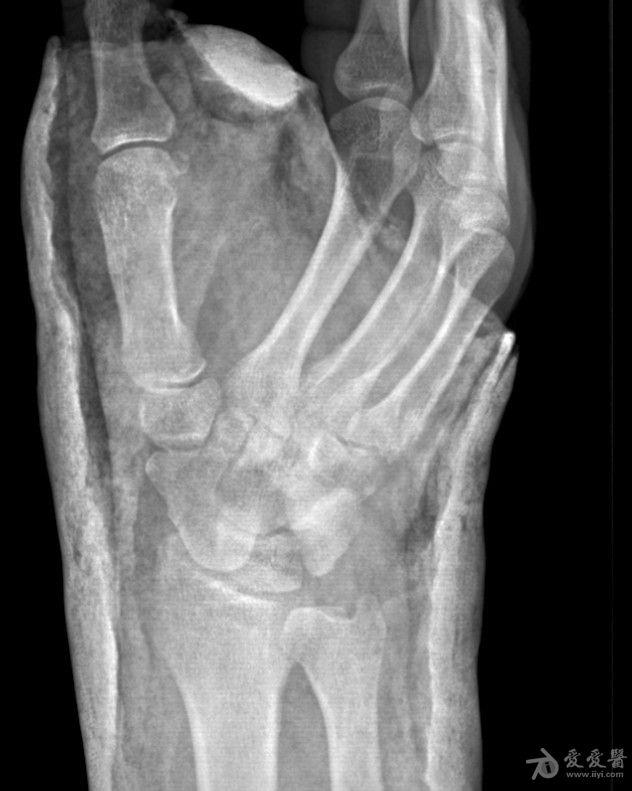

右手舟状骨骨折4个月

右手舟状骨骨折四个月,一直石膏保守治疗,拍片如下,请问,现在是手术治疗好还是继续保守治疗?